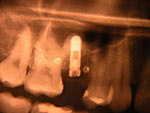

Die folgenden Patientenfälle sollen Ihnen einen Einblick in die Möglichkeiten der modernen Implantation geben.

Implantation – Patientenbeispiel 2: